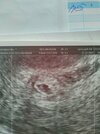

Na jednym zdjęciu mój Fasolek , a na drugim torbiel ..

Dzień dobry Kobietki , byłam wczoraj u lekarza prywatnie, lekarz znalazł na lewym jajniku dość dużą torbiel , małego krwiaka wokół pęcherzyka , w pęcherzyku jest już zarodek , prawdopodobnie młodsza ciąża niż według miesiączki , jeszcze ciężko było go zmierzyć ale słyszałam już tętno i widziałam na wykresie rytmiczne takie grube linie. Dostałam luteinę dopochwowo plus ten Duphaston. Odpowiedział na wszystkie nurtujące mnie pytania ale jeszcze nadal czuję strach po tym jak powiedział że ciąża jest młodsza niż według tej miesiączki która podałam . Czy mam się czym martwić ? Przed poronieniem również słyszałam że ciąża jest młodsza .. stąd moje obawy .